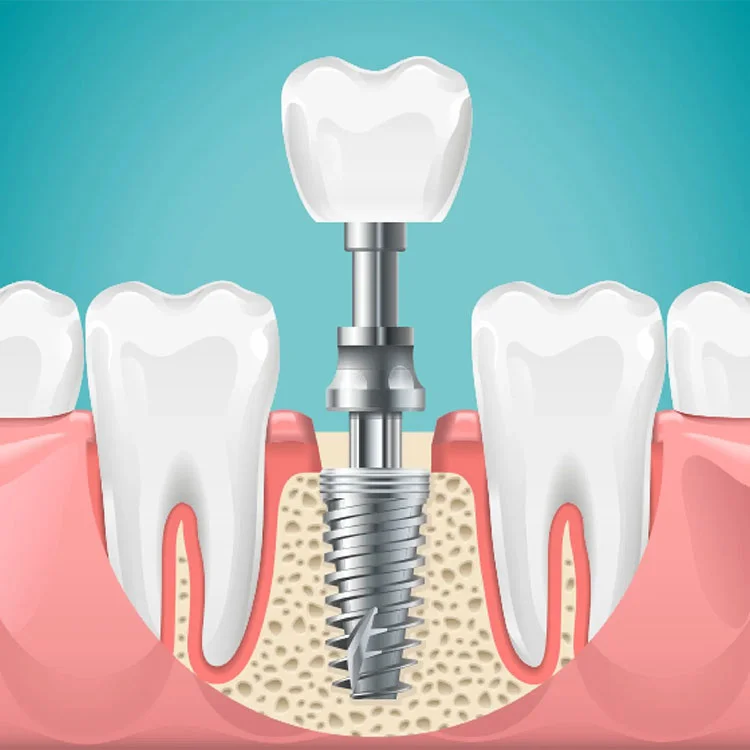

Dental Implants

Permanent and Natural-Looking Tooth Replacement with Dental Implants

G.S. Dental is a premier clinic specializing in dental implants. If you're missing a tooth & looking for a reliable, natural-looking replacement, you've come to the right place! We use the latest technology & techniques to ensure precise dental implant placement and exceptional results tailored to your unique needs. Rediscover your smile and confidence with our expert dental care.

Implant-Supported Dentures

Secure and stable dentures anchored by implants for better functionality.

Zygomatic Implants

Advanced option for patients with severe bone loss, using cheekbone support.